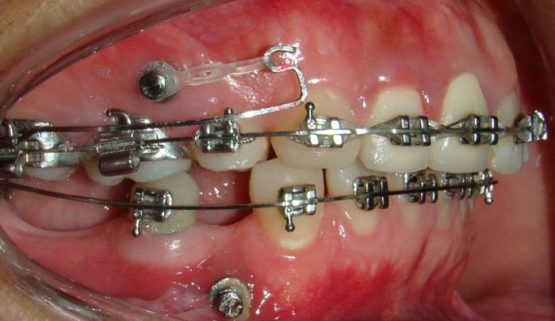

Răng lấy tủy có thể niềng. Nhưng quá trình niềng răng sẽ trở nên khó khăn hơn so với trường hợp răng còn nguyên tủy. Khi tủy răng bị lấy đi, răng sẽ trở nên giòn và dễ bị vỡ, làm cho việc gắn mắc cài trở nên khó khăn hơn và có nguy cơ làm tổn thương răng hơn.

Bạn nên thông báo với bác sĩ chỉnh nha về tình trạng và số lượng răng đã lấy tủy để được tư vấn và lên phác đồ điều trị phù hợp. Nếu số lượng răng đã lấy tủy quá nhiều (chiếm hơn 50% răng trên cung hàm) hoặc răng bị tổn thương nặng, bạn không nên niềng răng vì có thể gây ra nhiều rủi ro. Trong trường hợp này, bác sĩ có thể đề xuất các phương pháp điều trị khác như cấy ghép răng hoặc mài răng để tạo ra không gian đủ cho việc niềng răng.

Ngoài ra, việc niềng răng sau khi đã lấy tủy cũng cần phải được thực hiện cẩn thận để tránh tổn thương đến răng và đảm bảo sức khỏe toàn diện. Bạn cần phải tuân thủ các chỉ dẫn của nha sĩ để chăm sóc răng miệng một cách đúng cách, tránh ăn những thực phẩm quá cứng hoặc dẻo quá khó nuốt, và đến kiểm tra định kỳ để bác sĩ chỉnh nha có thể theo dõi tình trạng răng.